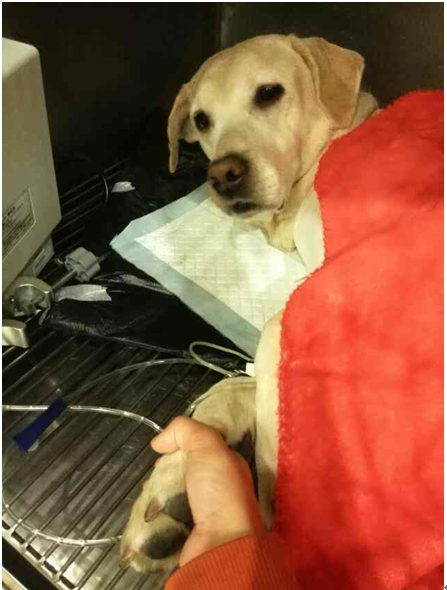

治疗中的苏格